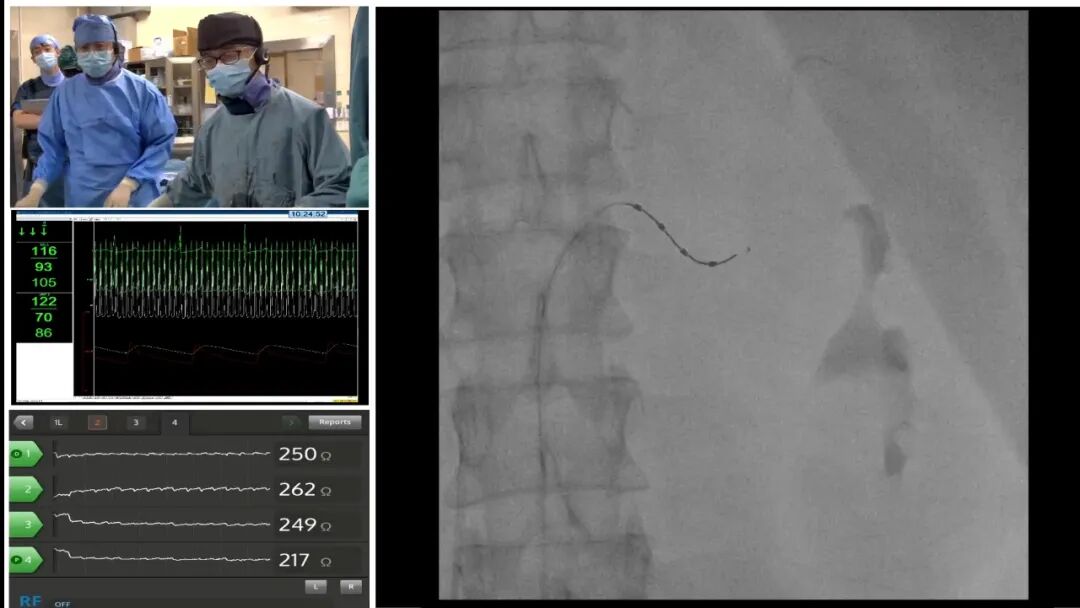

Carto Innovation GREAT PFA Live Case

逸仙例鉴·新脉领航PFA手术联播专场

房颤新技术专场

心律失常论坛深入探讨复杂心律失常的导管消融策略,展示高密度标测、脉冲电场消融等新技术应用。同时,关注遗传性心律失常的基因诊断与风险管理,以及植入式心脏装置的临床进展。心力衰竭论坛聚焦心力衰竭的最新药物治疗进展,新型药物的临床应用与循证更新,探讨心衰器械治疗的适应证优化。冠心病论坛重点探讨复杂冠脉病变的介入治疗策略选择与器械进展。同时,结合腔内影像学与功能学评估,讨论精准介入治疗与优化治疗结果的临床路径。高血压论坛深入探讨难治性高血压的病因评估与管理策略,分享高血压相关靶器官损害(心、肾、脑)的防治。结构性心脏病及大血管病论坛全面展示经导管介入技术的最新成果,进一步分享了经导管主动脉瓣置换/植入术、二尖瓣/三尖瓣介入治疗、左心耳封堵术的临床数据与操作技巧。心脏性猝死论坛深入探讨心脏性猝死的危险分层与预测模型,强调在心肌病、心衰等患者群体中的预防策略。房颤论坛集中讨论房颤的综合管理,关注卒中预防以及房颤合并其他疾病的管理。肿瘤心脏病论坛作为心血管与肿瘤学的交叉前沿,重点探讨抗肿瘤治疗相关心脏毒性的早期监测、风险评估、预防与处理策略。女医师联盟论坛则重点关注巴赫曼束起搏、CRT治疗方面的最新进展,对心房生理性起搏、心脏同步化治疗的优化进行了深入的探讨。